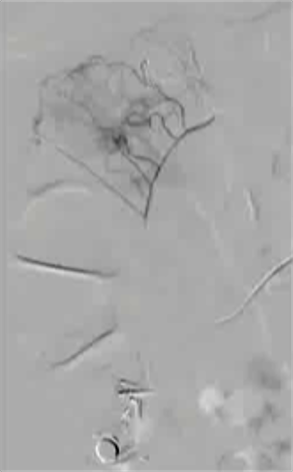

抗凝剂:肝素 溶栓药物:尿激酶、阿替普酶 ![]() 7 名患者 在动脉内内给予托拉唑啉、肝素、尿激酶进行血管造影操作 2 名患者出现出血性诱因情况 外科治疗 ![]() 回顾性分析(2002 年至 2008 年) 34 名患者(年龄 7 至 92 岁),36 例刺激性肠造影检查 全身性使用肝素 动脉内给药的血管扩张剂 11 名患者(占 31%)出现出血情况的检测结果。 10 栓塞治疗 病例1 消化道大出血 血压 70/40mmGg

病例三 77岁女性复发性胃肠道出血,需要多次输血并入住ICU。(d)栓塞后无外渗。箭头指向栓塞部位。